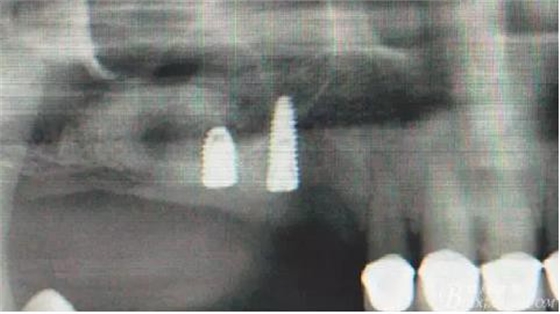

術(shù)后X光片。